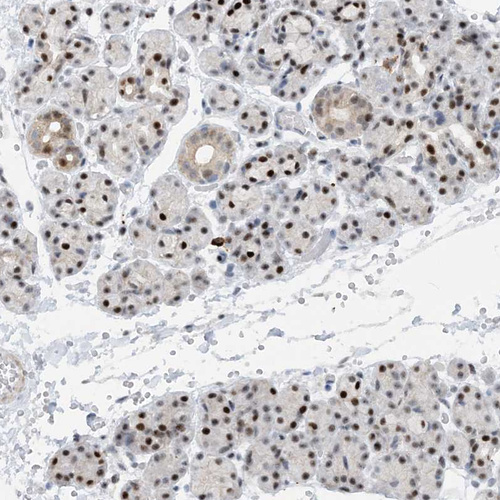

Immunohistochemical staining of human salivary gland shows strong nuclear positivity in glandular cells in addition to weak cytoplasmic positivity.